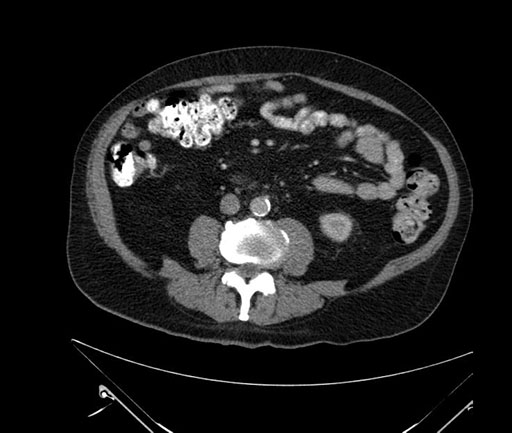

Imaging Analysis

Look through the patient's CT scan to identify any areas of concern for the necessary procedure.

Based on your CT findings, which issue(s) would give reason for "planned slowing down moment(s)" in this case?